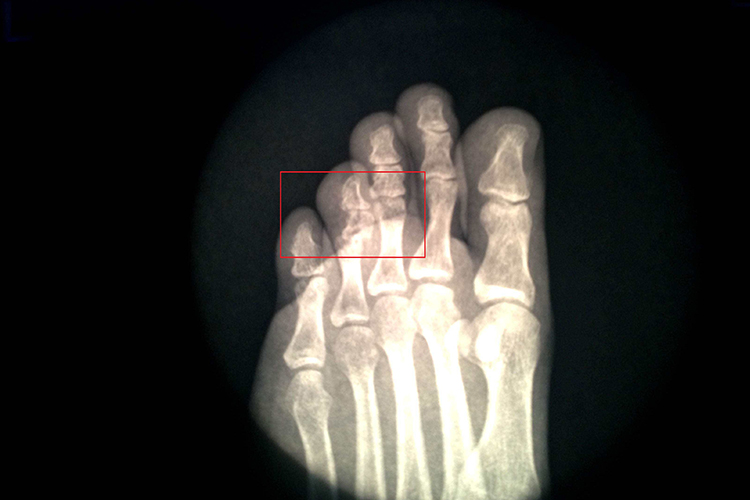

近节趾骨骨折多无明显移位,近节趾骨骨折由于骨间肌和蚓状肌的牵拉,向跖侧成角,使足趾呈爪状畸形,在路面形成骨性硬结,有明显的触痛,会给行走带来困难。X线等影像学检查可见,双籽骨或三籽骨为双侧性,边缘光滑。